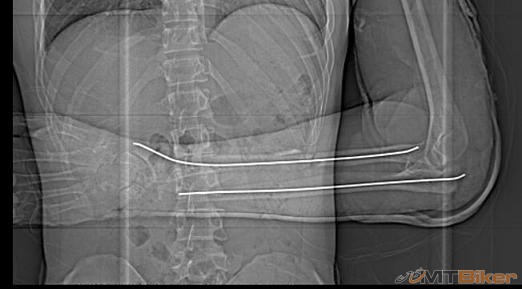

Pridám aj ja zo svojho. Stalo sa pred dvoma rokmi v júli, keby aspoň niekde v teréne ale prd! ráno pri ceste do práce. Čakal som na priechode pod Novým mostom v BA na zelenú, keď naskočila postavil som sa do pedálov a naplno zabral - raz, dva a na tretíkrát preskočila reťaz a ja som hodil ukážkového tigra cez riadidlá. Smola bola, že som si to nasmeroval ľavým lakťom priamo na obrubník takže ten si odniesol celých 90 kg mojej skromnej hmotnosti. Keby som padol na hlavu nič by sa nestalo ale na prilbe nebol ani šrabanček, rovnako nikde na tele nič ani ranka, akurát na stehne zozadu modrina ako dve dlane - od sedla. Takže všetko si odniesol ľavý lakeť. Výsledok vidíte: otvorená trieštivá zlomenina ľavého lakťa, krvi tam po mne zostalo ako po zabíjačke, odvoz RZP na Kramáre, 4 hodiny skladanie na operačke - titanová dlaha a 10 skrutiek. Odvtedy som na bike-u nesedel. Ako som už inde písal zanechalo to bohužiaľ trvalé následky, tá ruka už nefunguje tak ako by mala ale k bike-u ma to znovu ťahá, trochu rekreácie by som si rád doprial. Tak si to vychutnajte

Ja som prave s predlaktim a laktovym klbom doma za spolocnosti drotov a srobu. Mna zrazilo auto na bajku (presiel do protismeru a tam si ma nasiel).